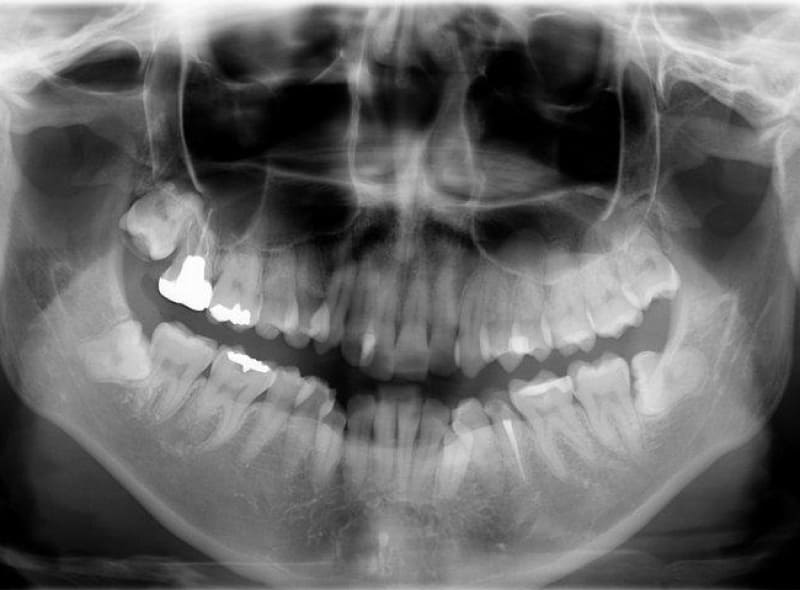

精密検査

治療方針が決定しましたらレントゲンや口腔内写真、口腔外写真、噛み合わせ検査、歯周病検査など精密検査を行います。